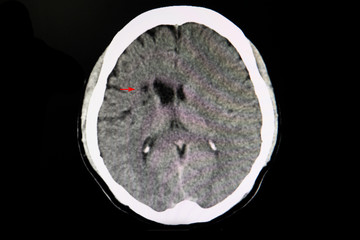

CT brain of a stroke patient..

CT brain of a stroke patient